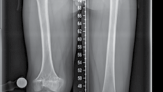

| 49. Two rings per bone segment (near and far) | |||

| 50. Two wires/half-pins per ring | |||

| 51. Four connecting, threaded rods between rings (Figure 15.9) 52. Fibular osteotomy | |||

| 1. Mid-diaphyseal avoids neurovascular structures | |||

| 53. Fix fibula (proximal and distal), to avoid joint subluxation | |||

| Figure 15.9 Radiograph of tibial Ilizarov frame for lengthening. | |||